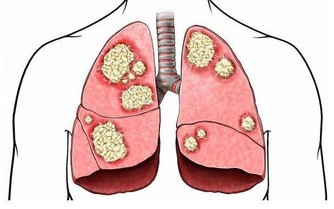

在目前的中國,看病真的好貴,若不幸得了癌症,簡直就是一病回到解放前。更糟糕的是,查出的癌症大多是晚期,有錢也未必治得好,腸癌就是其中典型的例子。

數據顯示腸癌現狀在我國,每年新增結直腸癌竟達40萬例,平均每5min就有1人死於腸癌。

早期腸癌的臨床診斷率僅為11%-15%,治愈率高,術後5年生存率可達95%;而超過80%的患者確診腸癌時,

已發展至中晚期,治愈效果並不理想,5年生存率只有5%左右。

預防腸癌,三大習慣不可少腸癌已躍居所有腫瘤中發病率的第三,且發病人數逐年增長,預防腸癌勢在必行!